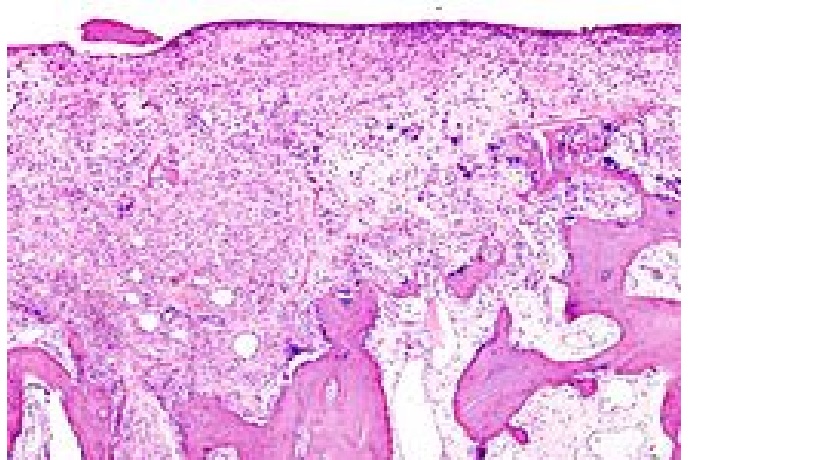

Wyniki badania oceniającego przydatność artroskopii w chorobie zwyrodnieniowej stawu kolanowego (czsk) wskazują, iż może to być przydatna metoda postępowania w przypadku określonej grupy pacjentów. Artroskopia, jako metoda leczenia w czsk, budzi wiele kontrowersji. Wyniki niektórych opublikowanych badań, w tym kontrolowanych placebo, wskazują, że debridement oraz artroskopowy laważ, w przypadku czsk, mają skuteczność zbliżoną do placebo. Z drugiej jednak strony istneją doniesienia, że artroskopia może być skutecznym narzędziem w terapii tych chorych. O opinię, drogą elektronicznego kwestionariusza, poproszono grupę 170 europejskich specjalistów zajmujących się na codzień wykonywaniem artroskopii (co najmniej dziesięcioletnie doświadczenie w wykonywaniu atroskopii, wykonywanie ponad 100 procedur rocznie). W większości byli to lekarze prywatnie praktykujący, a także pracujący w szpitalach uniwersyteckich oraz placówkach publicznych. Kwestionariusz obejmował szeroką problematykę od wskazań, po przydatność różnych metod artroskopowych w postępowaniu w czsk. Odpowiedzi stopniowano w sześciostopniowej skali od ,,doskonały" po ,, brak wskazań". Jednym z kluczowych problemów była skuteczność artroskopii w różnych postaciach czsk – łagodnej i zaawansowanej. Blisko 2/3 ankietowanych widziało przydatność artroskopii w czsk, z uwzględnieniem określonych wskazań. Przede wszystkim lepsze efekty uzyskiwane są u chorych z mniej zaawansowaną postacią choroby (1 i 2 stopień w skali Kellgren-Lawrence), blisko 40% nie zaleca wykonywania zabiegu w ciężkich postaciach osteoatrozy. Obecność obrzęku kości (szpiku) w badaniu MRI, niekorzystnie wpływa na skuteczność zabiegu. W tym wypadku nie zaleca sie wykonywania artroskopii (opinia ok. 60% badanych). Lepsze efekty leczenia uzyskiwane są u młodszych chorych (poniżej 60 roku życia) oraz z krócej trwającymi objawami klinicznymi (poniżej 6 miesięcy). Większość badanych opowiedziała się przeciwko wykonywaniu laważu, atroskopii w artrofibrozie oraz usuwaniu osteofitów.